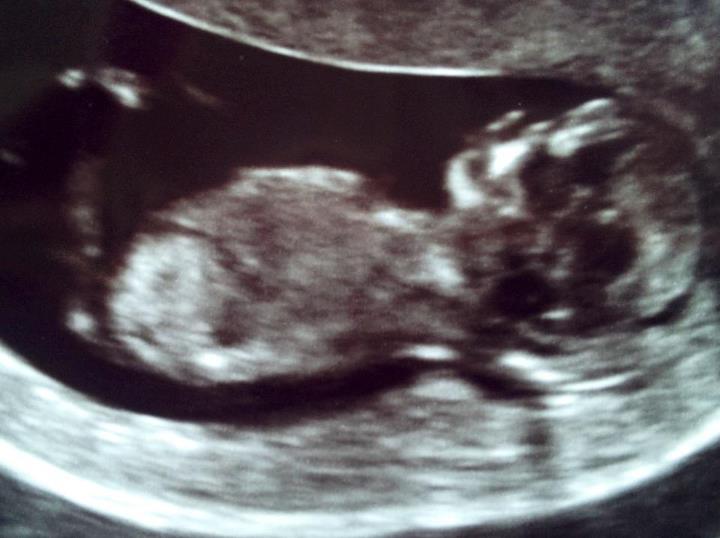

Last image is a profile but doctor (genetics) said it showed no "bits"

Attachment 3950

Skull guesses if no nub is seen???? :) thanks everyone!!!!